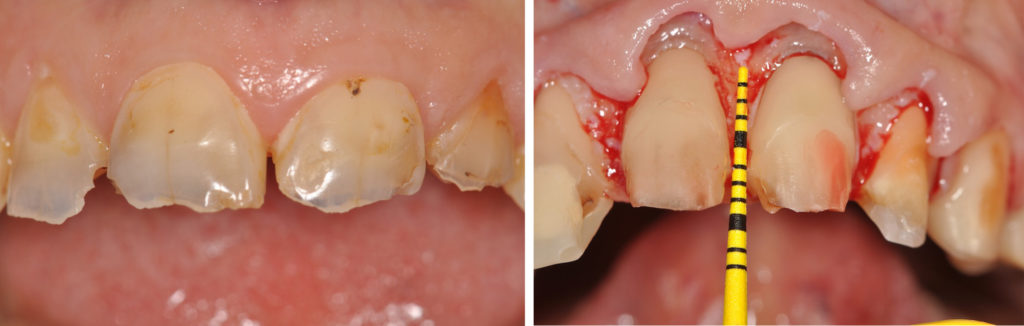

• renforcement et aménagements pré-prothétiques des tissus parodontaux : greffes conjonctives sur 13, 44 et 45, alignement des collets (Fig. 7a, b et c),

Le biotype parodontal est fin. On note des récessions gingivales sur les dents et dont certaines sont très proches de la ligne de jonction muco-gingivale. L’alignement des collets des incisives maxillaires est asymétrique.